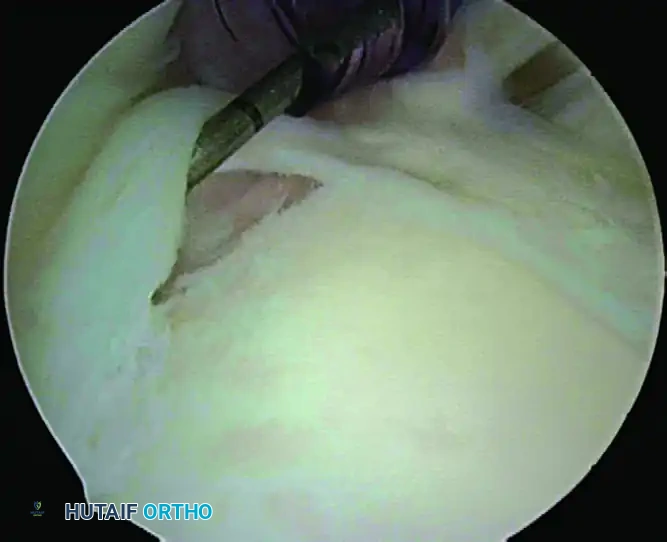

Step 2: Bone Bed Preparation

Through the anterior portal, introduce a motorized shaver or an arthroscopic rasp.

Elevate the detached superior labrum and prepare the bone bed on the superior neck of the glenoid, directly beneath the footprint of the biceps anchor.

Preparation of the bone bed on the superior neck of the glenoid using a motorized shaver. Care is taken to preserve the bony architecture.

Surgical Warning: Débride the soft tissues carefully down to a bleeding base of cancellous bone to promote biological healing. However, do not remove bone. Aggressive burring can destroy the superior glenoid rim, compromising the bony bumper and leading to anchor pull-out or iatrogenic instability.